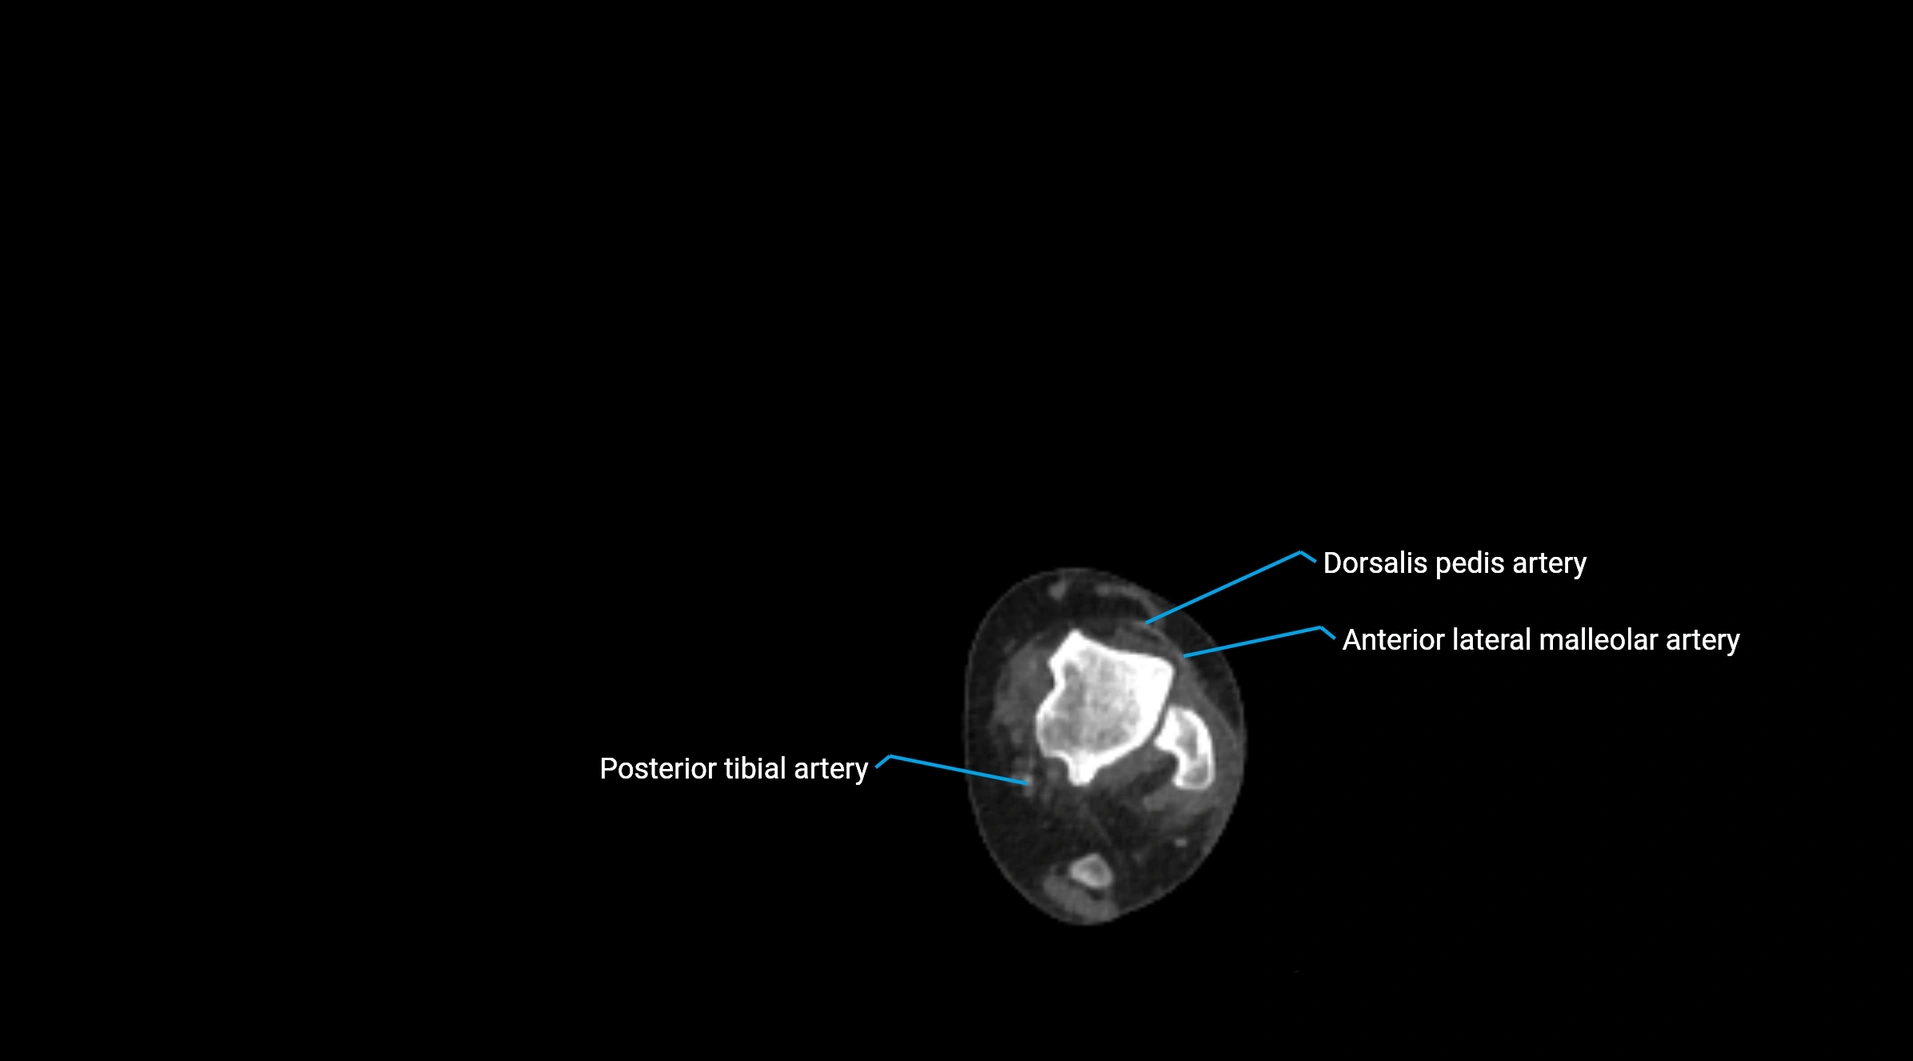

CT Appearance

Non-contrast CT:

• Appears as a tubular soft tissue structure anterior to vertebral bodies

• Calcified atherosclerotic plaques appear as hyperdense foci along the wall

• Useful for screening abdominal aortic aneurysm (AAA) size and mural calcification

Contrast-enhanced CT (CTA):

• Gold standard for abdominal aortic imaging

• Provides excellent detail of lumen, wall, aneurysm, thrombus, and branch vessels

• Multiplanar and 3D reconstructions help in aneurysm measurement, stent graft planning, and dissection evaluation

• Detects acute rupture, traumatic injury, or occlusion with high sensitivity